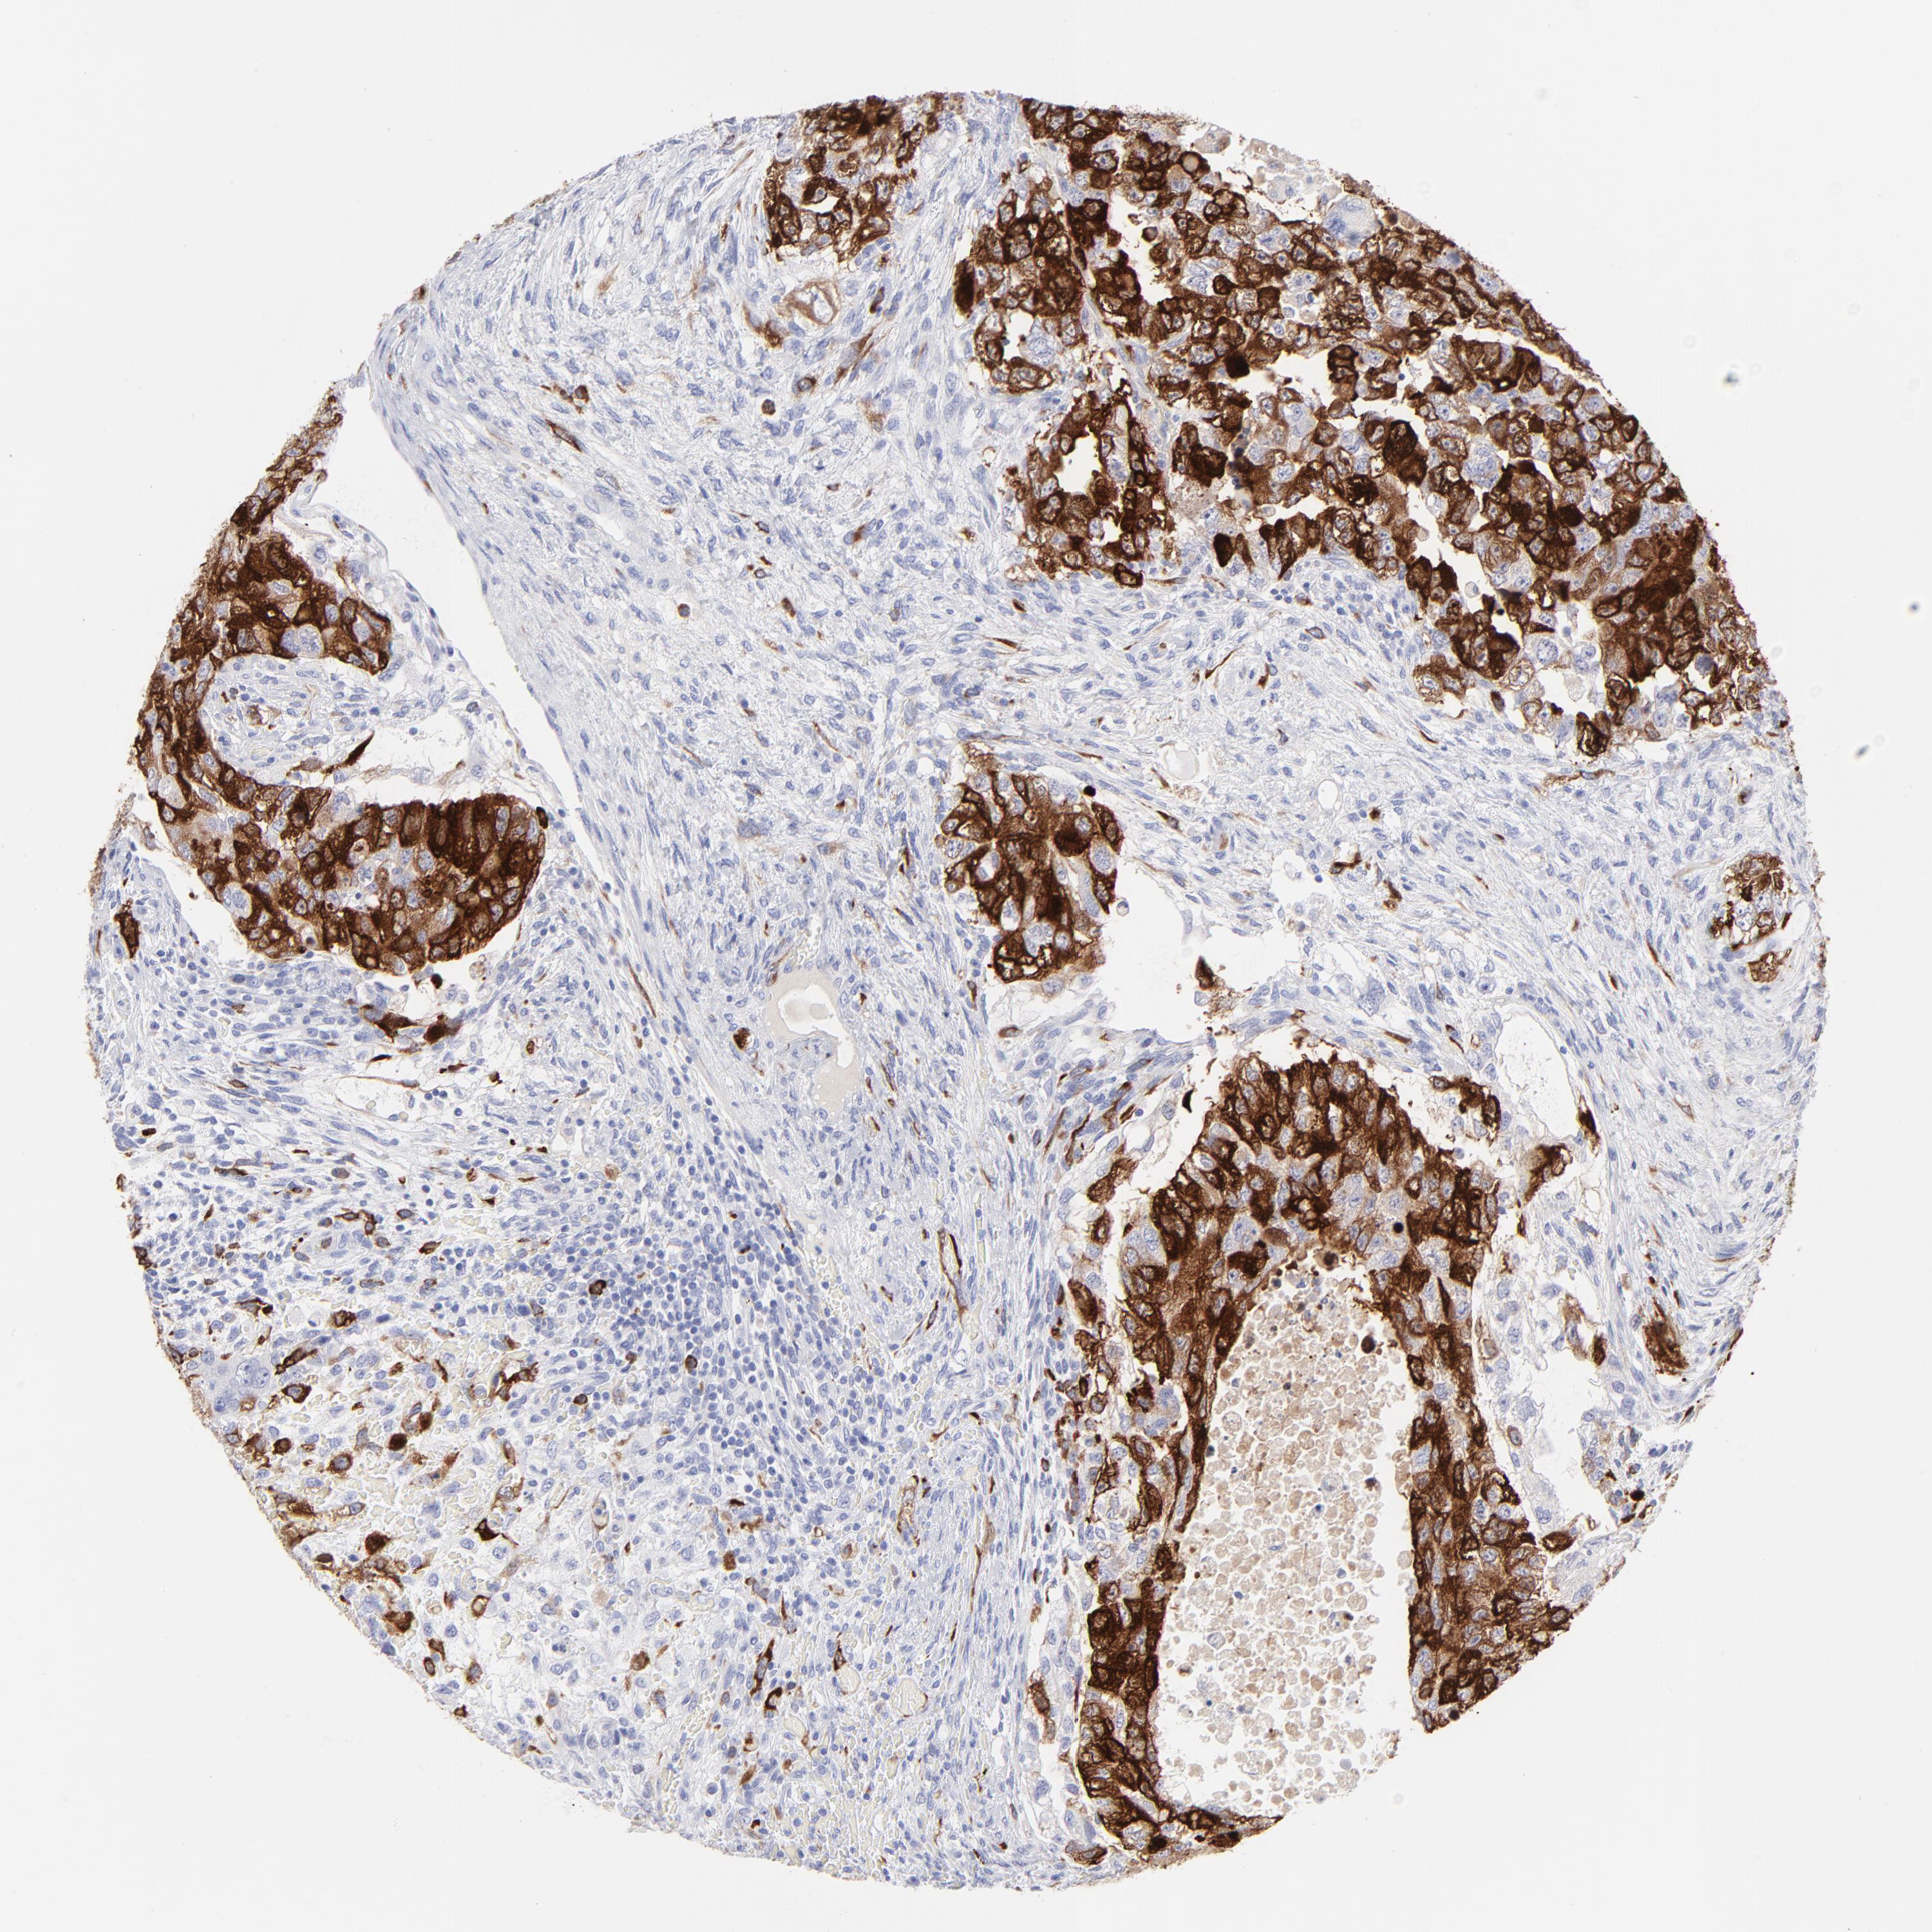

TESTIS CANCER - Protein expressioni

A mouse-over function shows sample information and annotation data. Click on an image to view it in a full screen mode. Samples can be filtered based on level of antibody staining by selecting one or several of the following categories: high, medium, low and not detected. The assay and annotation is described here.

Note that samples used for immunohistochemistry by the Human Protein Atlas do not correspond to samples in the TCGA dataset.

Antibody stainingi

Antibody staining in the annotated cell types in the current human tissue is reported as not detected, low, medium, or high, based on conventional immunohistochemistry profiling in selected tissues. This score is based on the combination of the staining intensity and fraction of stained cells.

Each image is clickable and will lead to virtual microscopy that enables deeper exploration of all samples and also displays staining intensity scores, fraction scores and subcellular localization as well as patient and tissue information for each sample.

Antibody HPA061448

Antibody CAB000115

Antibody CAB003804

Staining

High

Medium

Low

Not detected

Intensity

Strong

Moderate

Weak

Negative

Quantity

>75%

75%-25%

<25%

None

Location

Nuclear

Cytoplasmic/membranous

Cytoplasmic/membranous,nuclear

Seminoma, NOS

Carcinoma, Embryonal, NOS

Teratoma, malignant, NOS